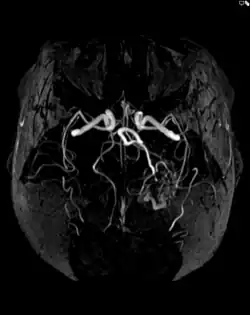

Magnetresonanztomographie/-angiographie

Die Auflösung der Bilder ist bei der Magnetresonanztomographie (MRT) oder Magnetresonanzangiographie (MRA) etwas höher und damit genauer. Vor allem Begleitveränderungen der AVM können besser dargestellt werden.[7] Das Verfahren arbeitet mit sich verändernden Magnetfeldern ohne Strahlenbelastung für den Patienten und ist damit als sicherere Methode anerkannt. Da es keine Strahlenbelastung gibt, wird die MRT auch bevorzugt bei regelmäßigen AVM-Nachsorgeuntersuchungen nach einer Behandlung eingesetzt. Die Untersuchungen dauern meist länger, teilweise bis zu einer Stunde. Auch bei der MRT können die Blutgefäße durch die gezielte Gabe von Kontrastmittel besser dargestellt werden.